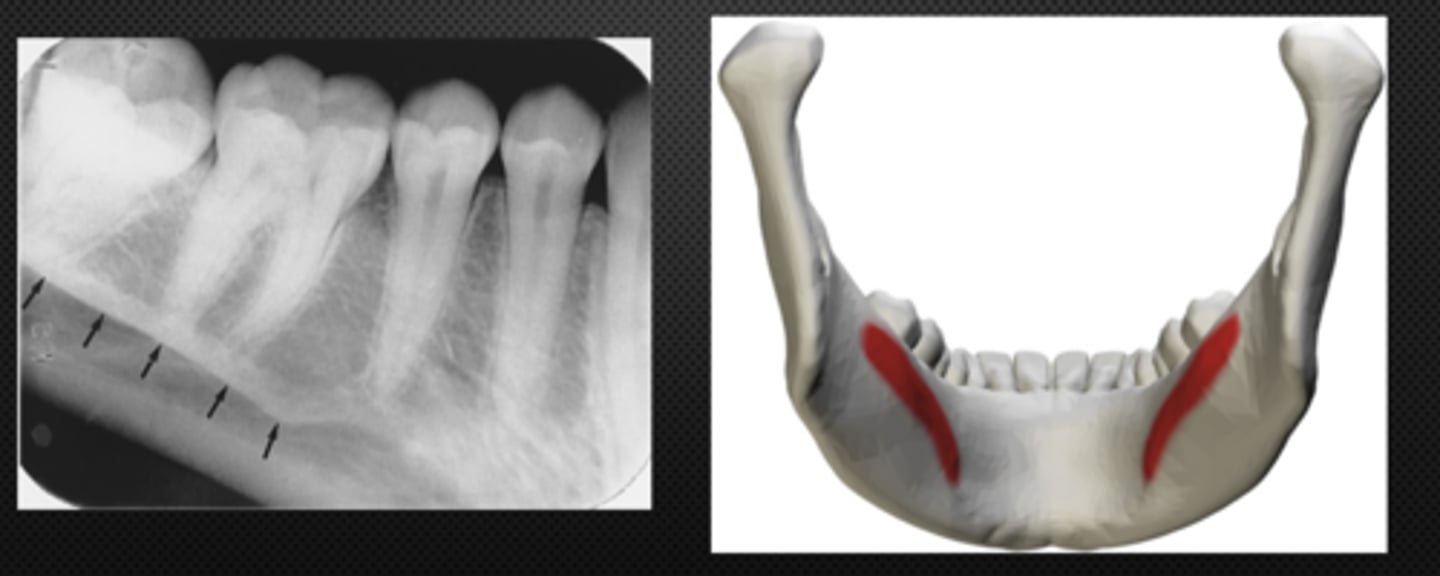

Mandibular canal

Identify the structure

<p>Identify the structure</p>

Identify the radiolucent structure

<p>Identify the radiolucent structure</p>

Nutrient canals (neurovascular canals)